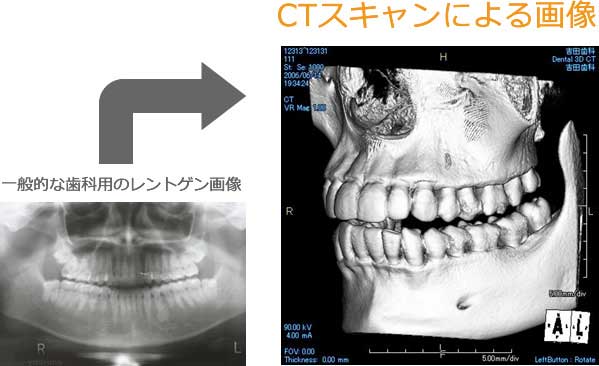

歯科用CTのご提案

歯科用CTによる診査・診断

治療を成功させるために「現状分析」は非常に大切となります。

現状を精密に把握してこそ、理想的な治療後の状態を決定することができ、適切な治療計画を立てることが可能となります。

そのため、歯、歯周組織、かみ合わせ、顎の骨、顎の骨の中の神経や血管の状態などを、精密に確認する必要があります。

精密に確認することで分析が可能となり、どのように治療を進めていくべきかを検討可能となります。